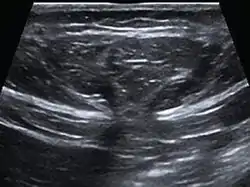

![]() تصوير بالموجات الصوتية لفتق شرسوفي في منطقة البطن. تصوير بالموجات الصوتية لفتق شرسوفي في منطقة البطن. | |

يستخدم التصوير بالموجات فوق الصوتية أيضًا لأغراض التشخيص.